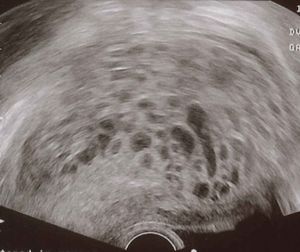

- Ultrasound: enlarged uterus with interspersed lucent and brighter areas ("snowstorm" appearance)